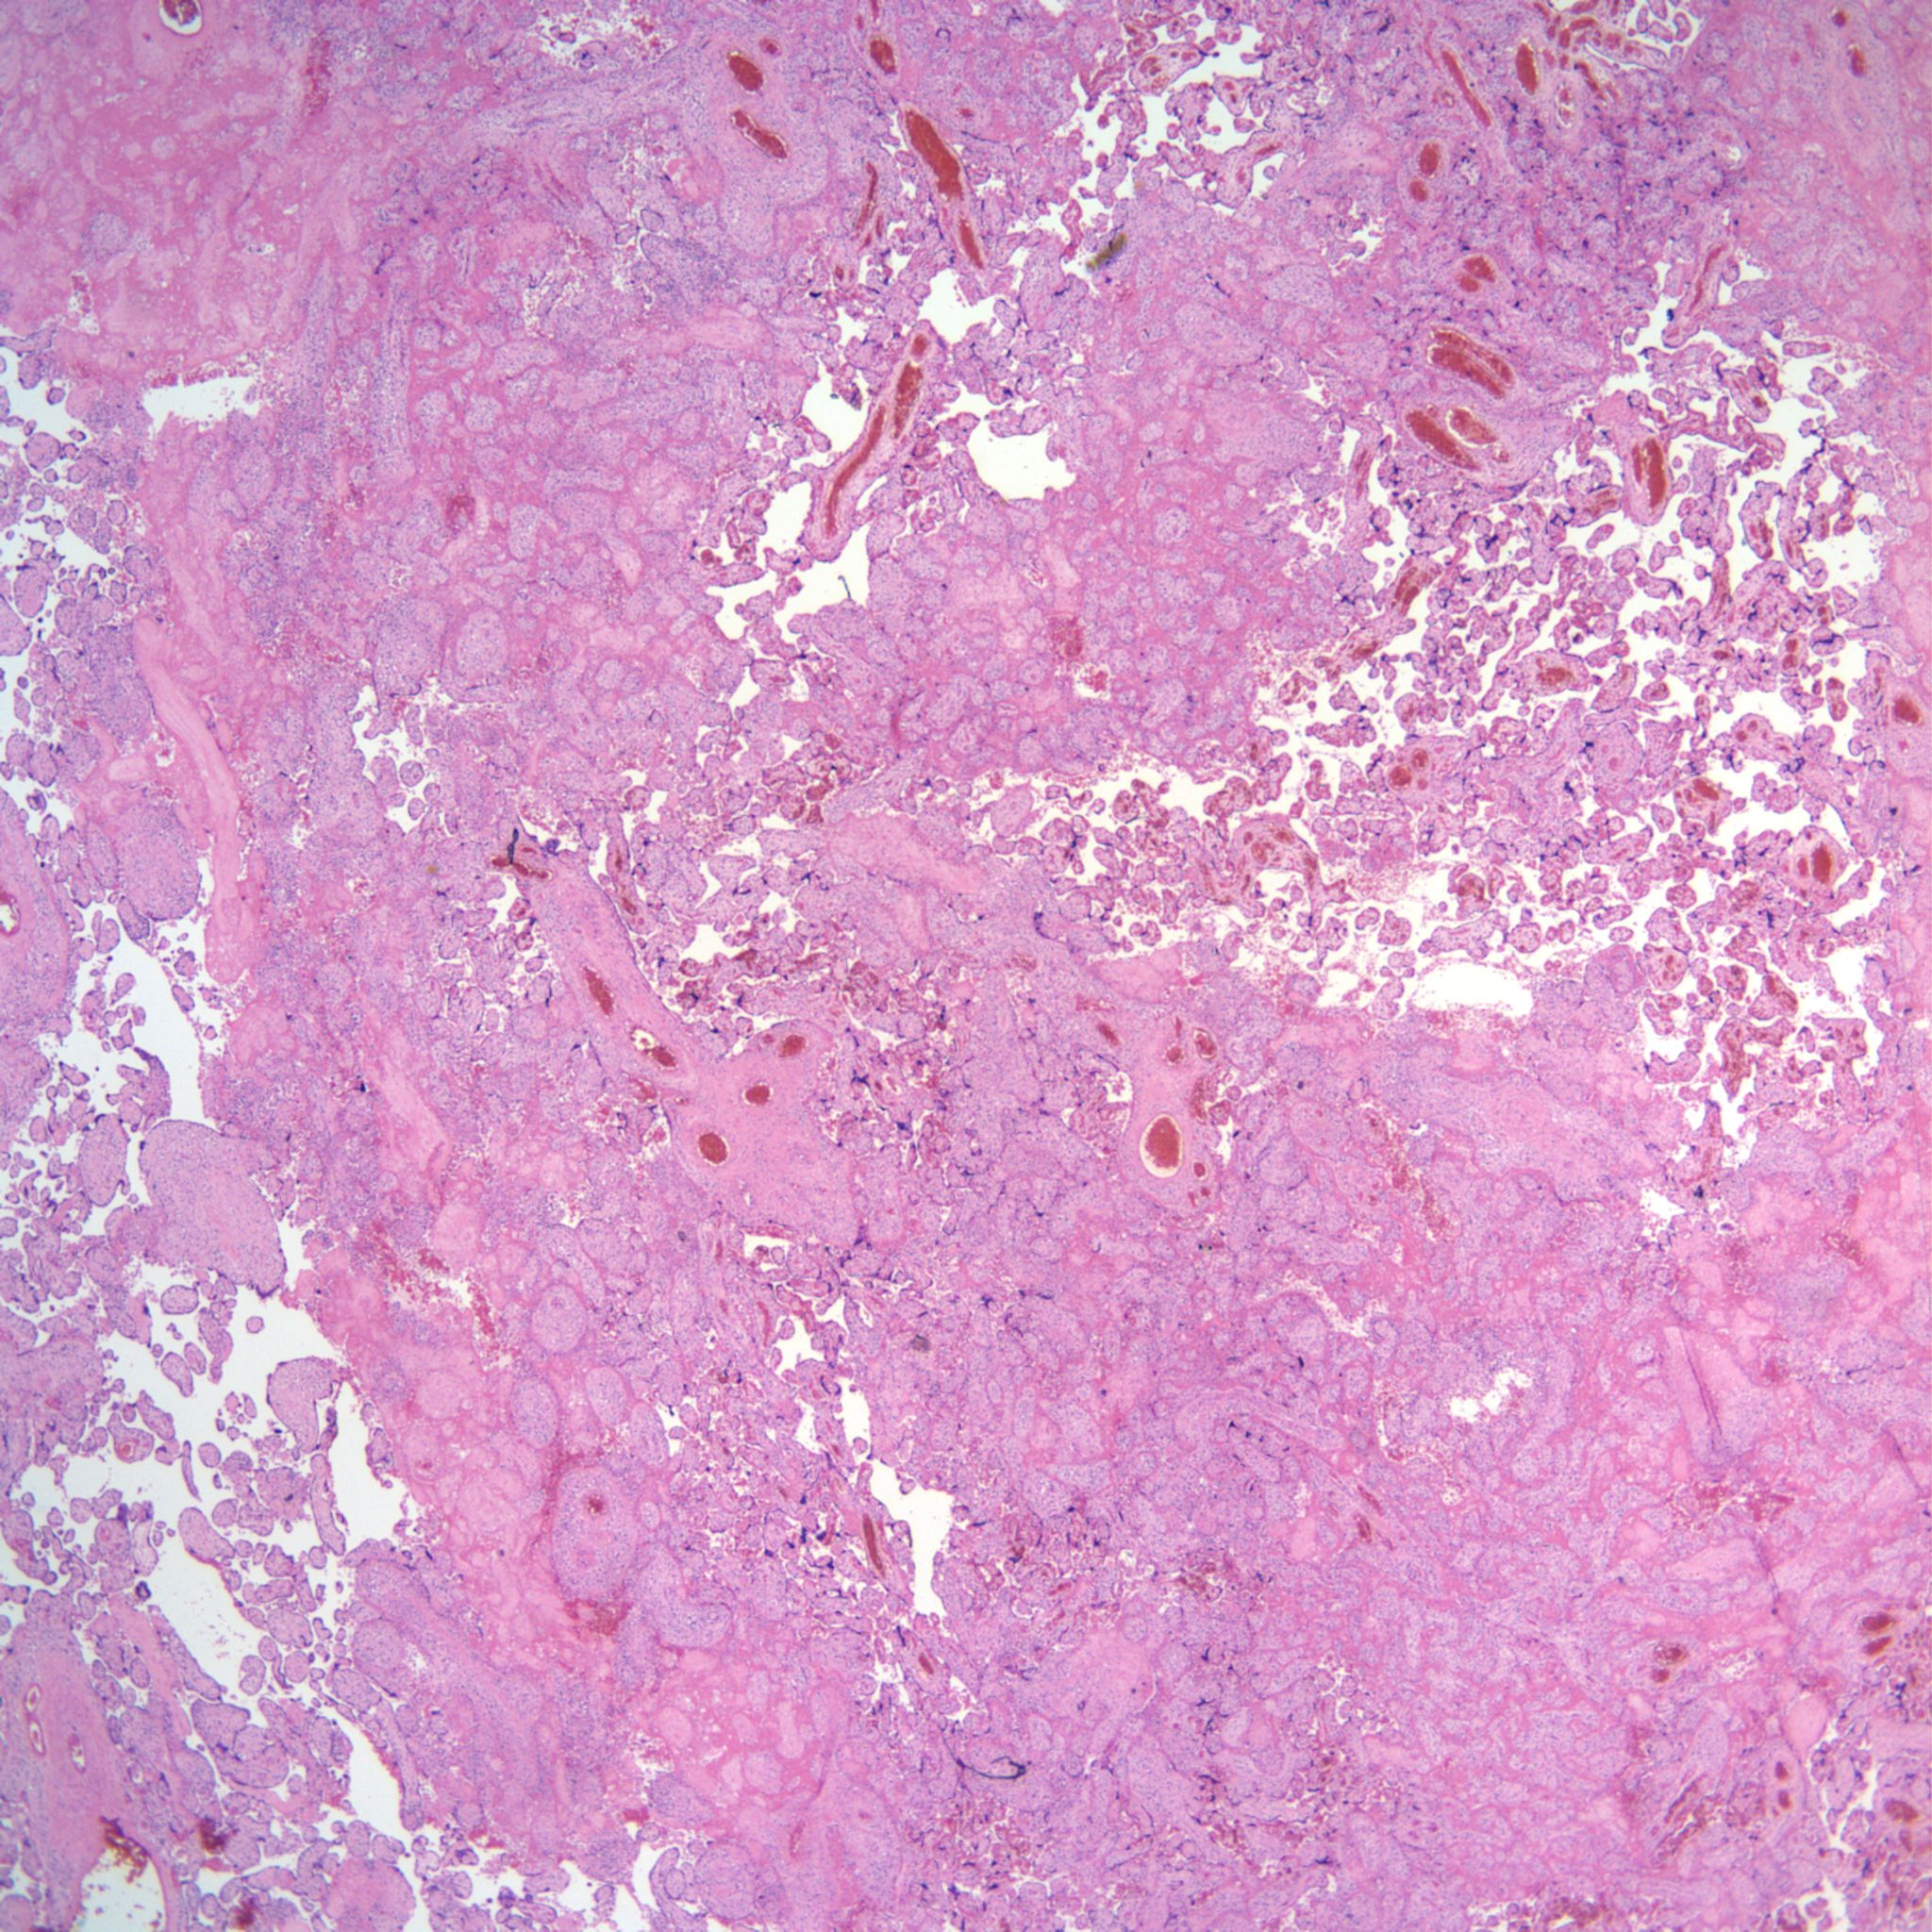

High Grade (massive) CHIV

Low Grade CHIV (5-50% of the intervillous space occupied by monocytes)